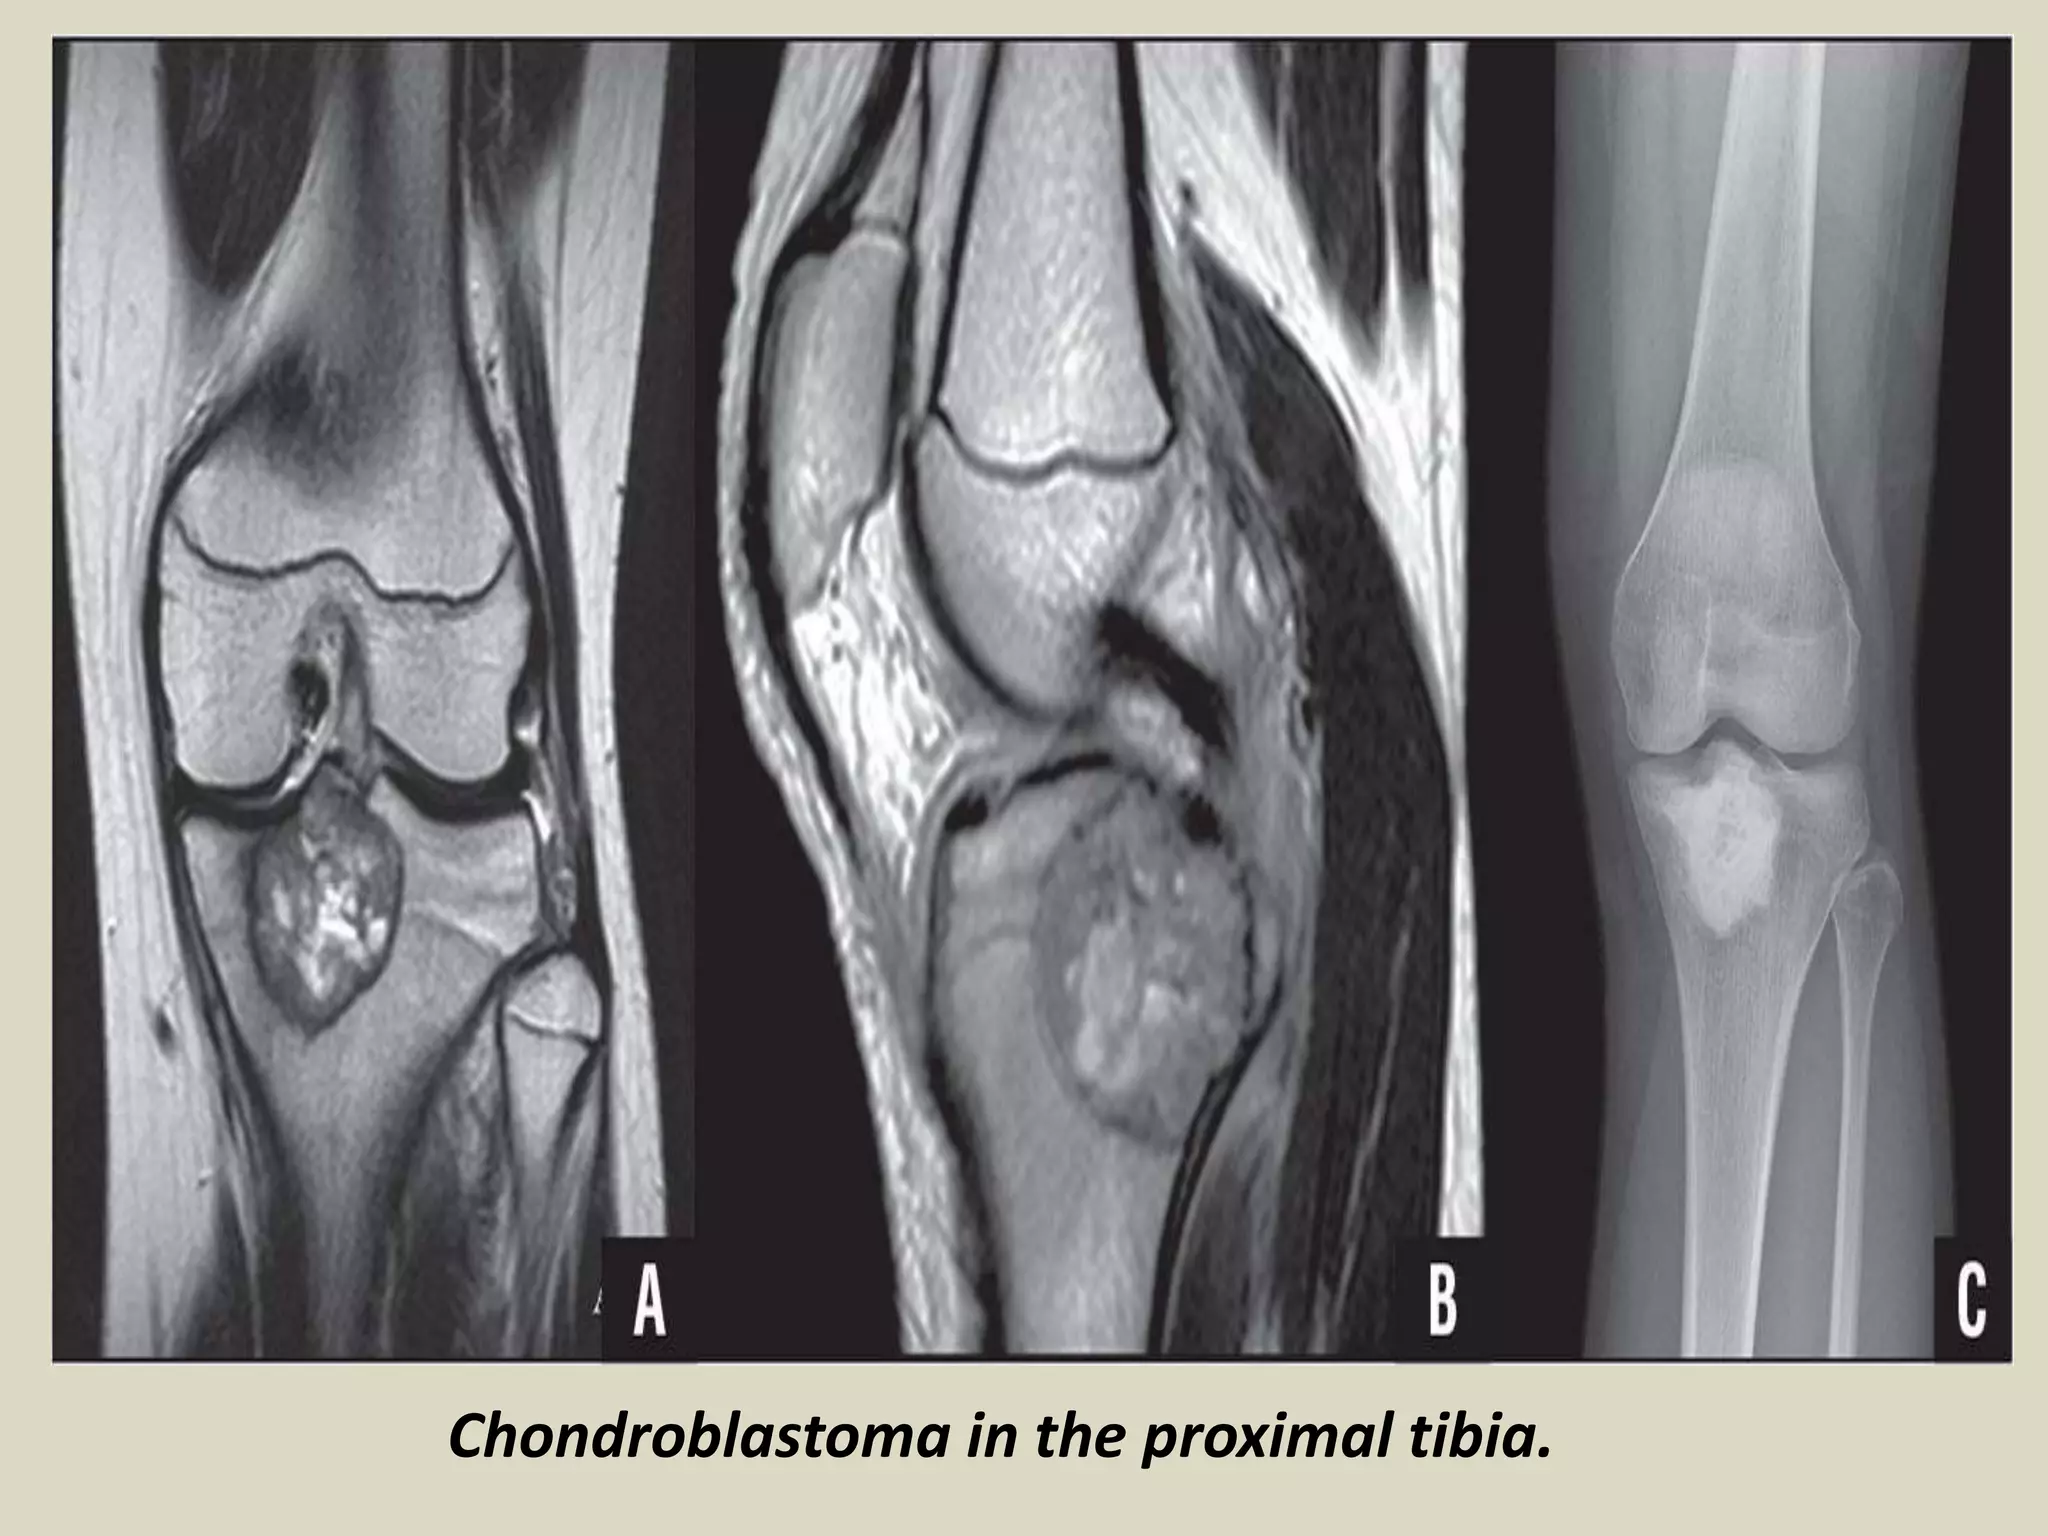

- Benign, cartilage producing neoplasm usually arising in the epiphyses of skeletally immature patients.

- Most patients are between 10 and 25 years of age at diagnosis and there is a male predominance.

- Usually arises in the epiphyses of the distal and proximal femur, followed by the proximal tibia

- Typically lytic, centrally or eccentrically placed, relatively small lesions (3 to 6 cm), occupying

- Shapely demarcated, with or without a thin sclerotic border.

- The presence of sclerotic rim, along with the younger age of the patient, helps to differentiate

chondroblastoma from giant cell tumor of bone, which generally lacks sclerotic border and occurs

- Often helpful, matrix calcifications are only visible in about 1/3 of patients.

Chondroblastoma in the proximal tibia.